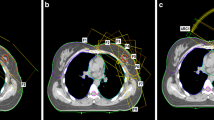

An exemplary representation of the dose distribution of the four techniques investigated for a patient with lung disease is shown in Fig. 2.